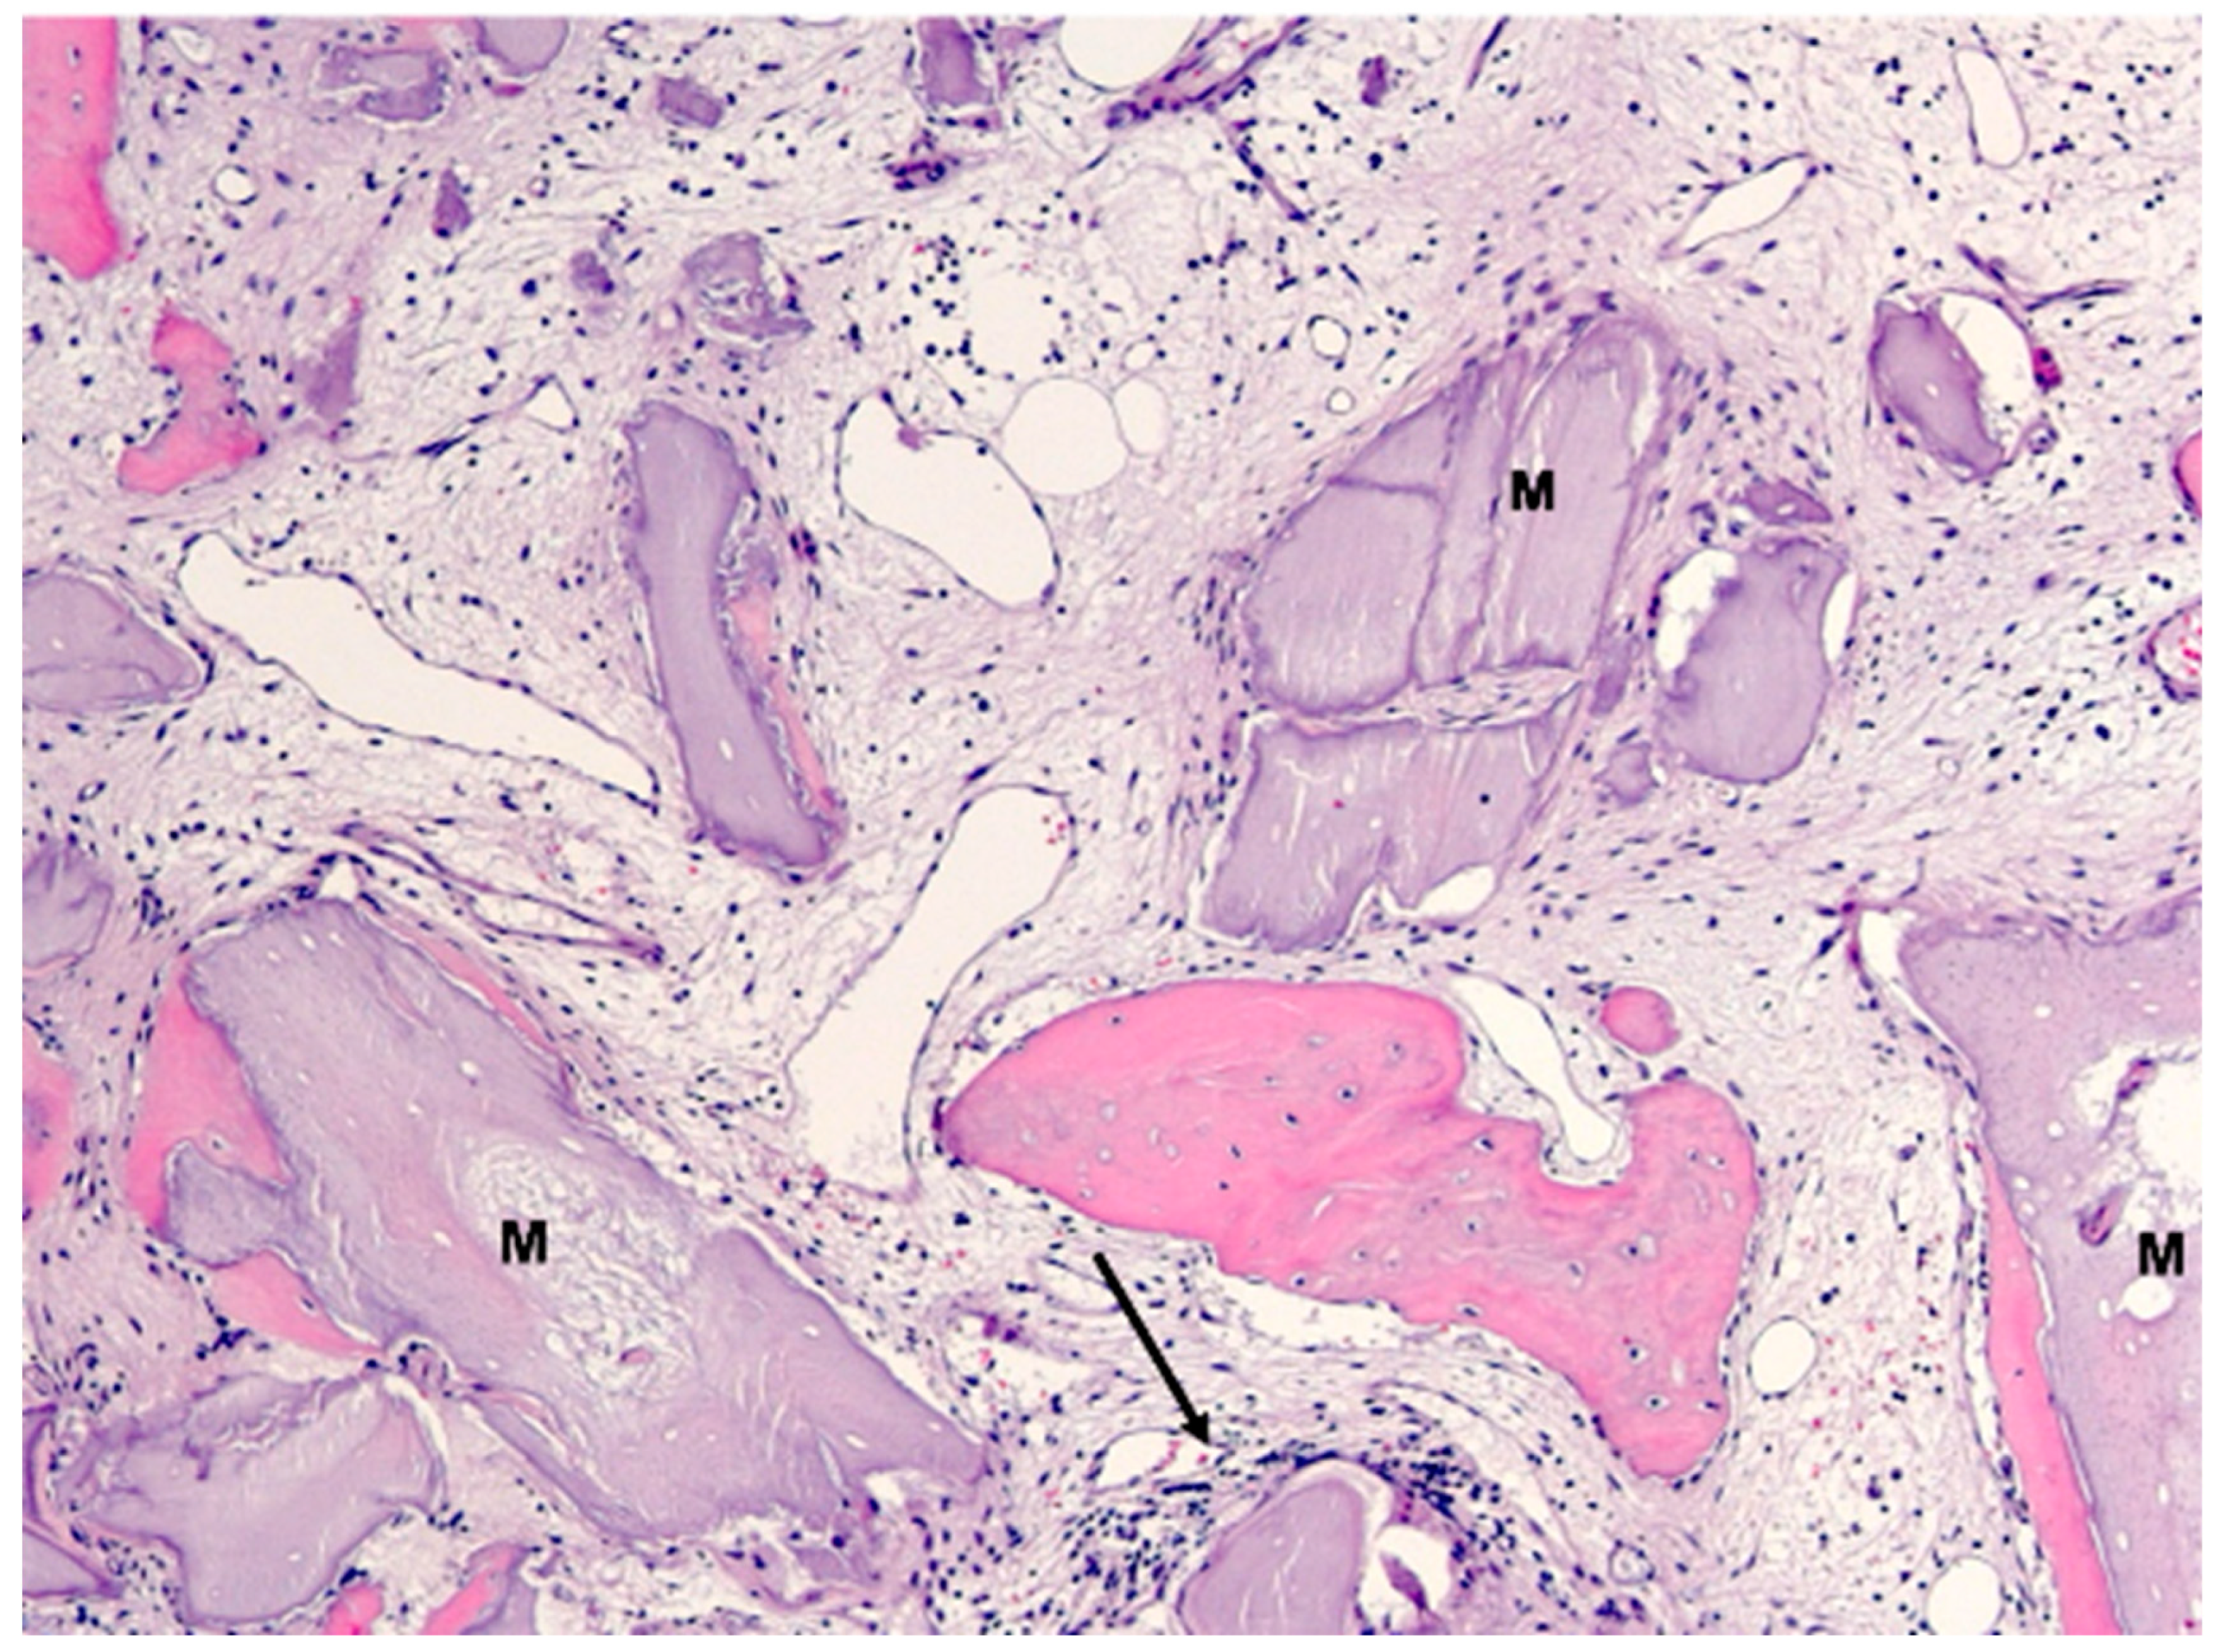

2.1. Histology

2.3. Histological Evaluation